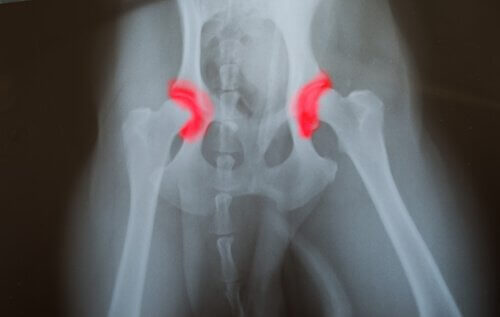

- Hoftedysplasi

Sammenlignet med store hunder som har et ubalansert kosthold, hadde de som spiste et balansert kosthold færre sykdommer forbundet med overvekst. Hoftedysplasi var en av de vanligste sykdommene hos store hunder som fikk for mye mat.